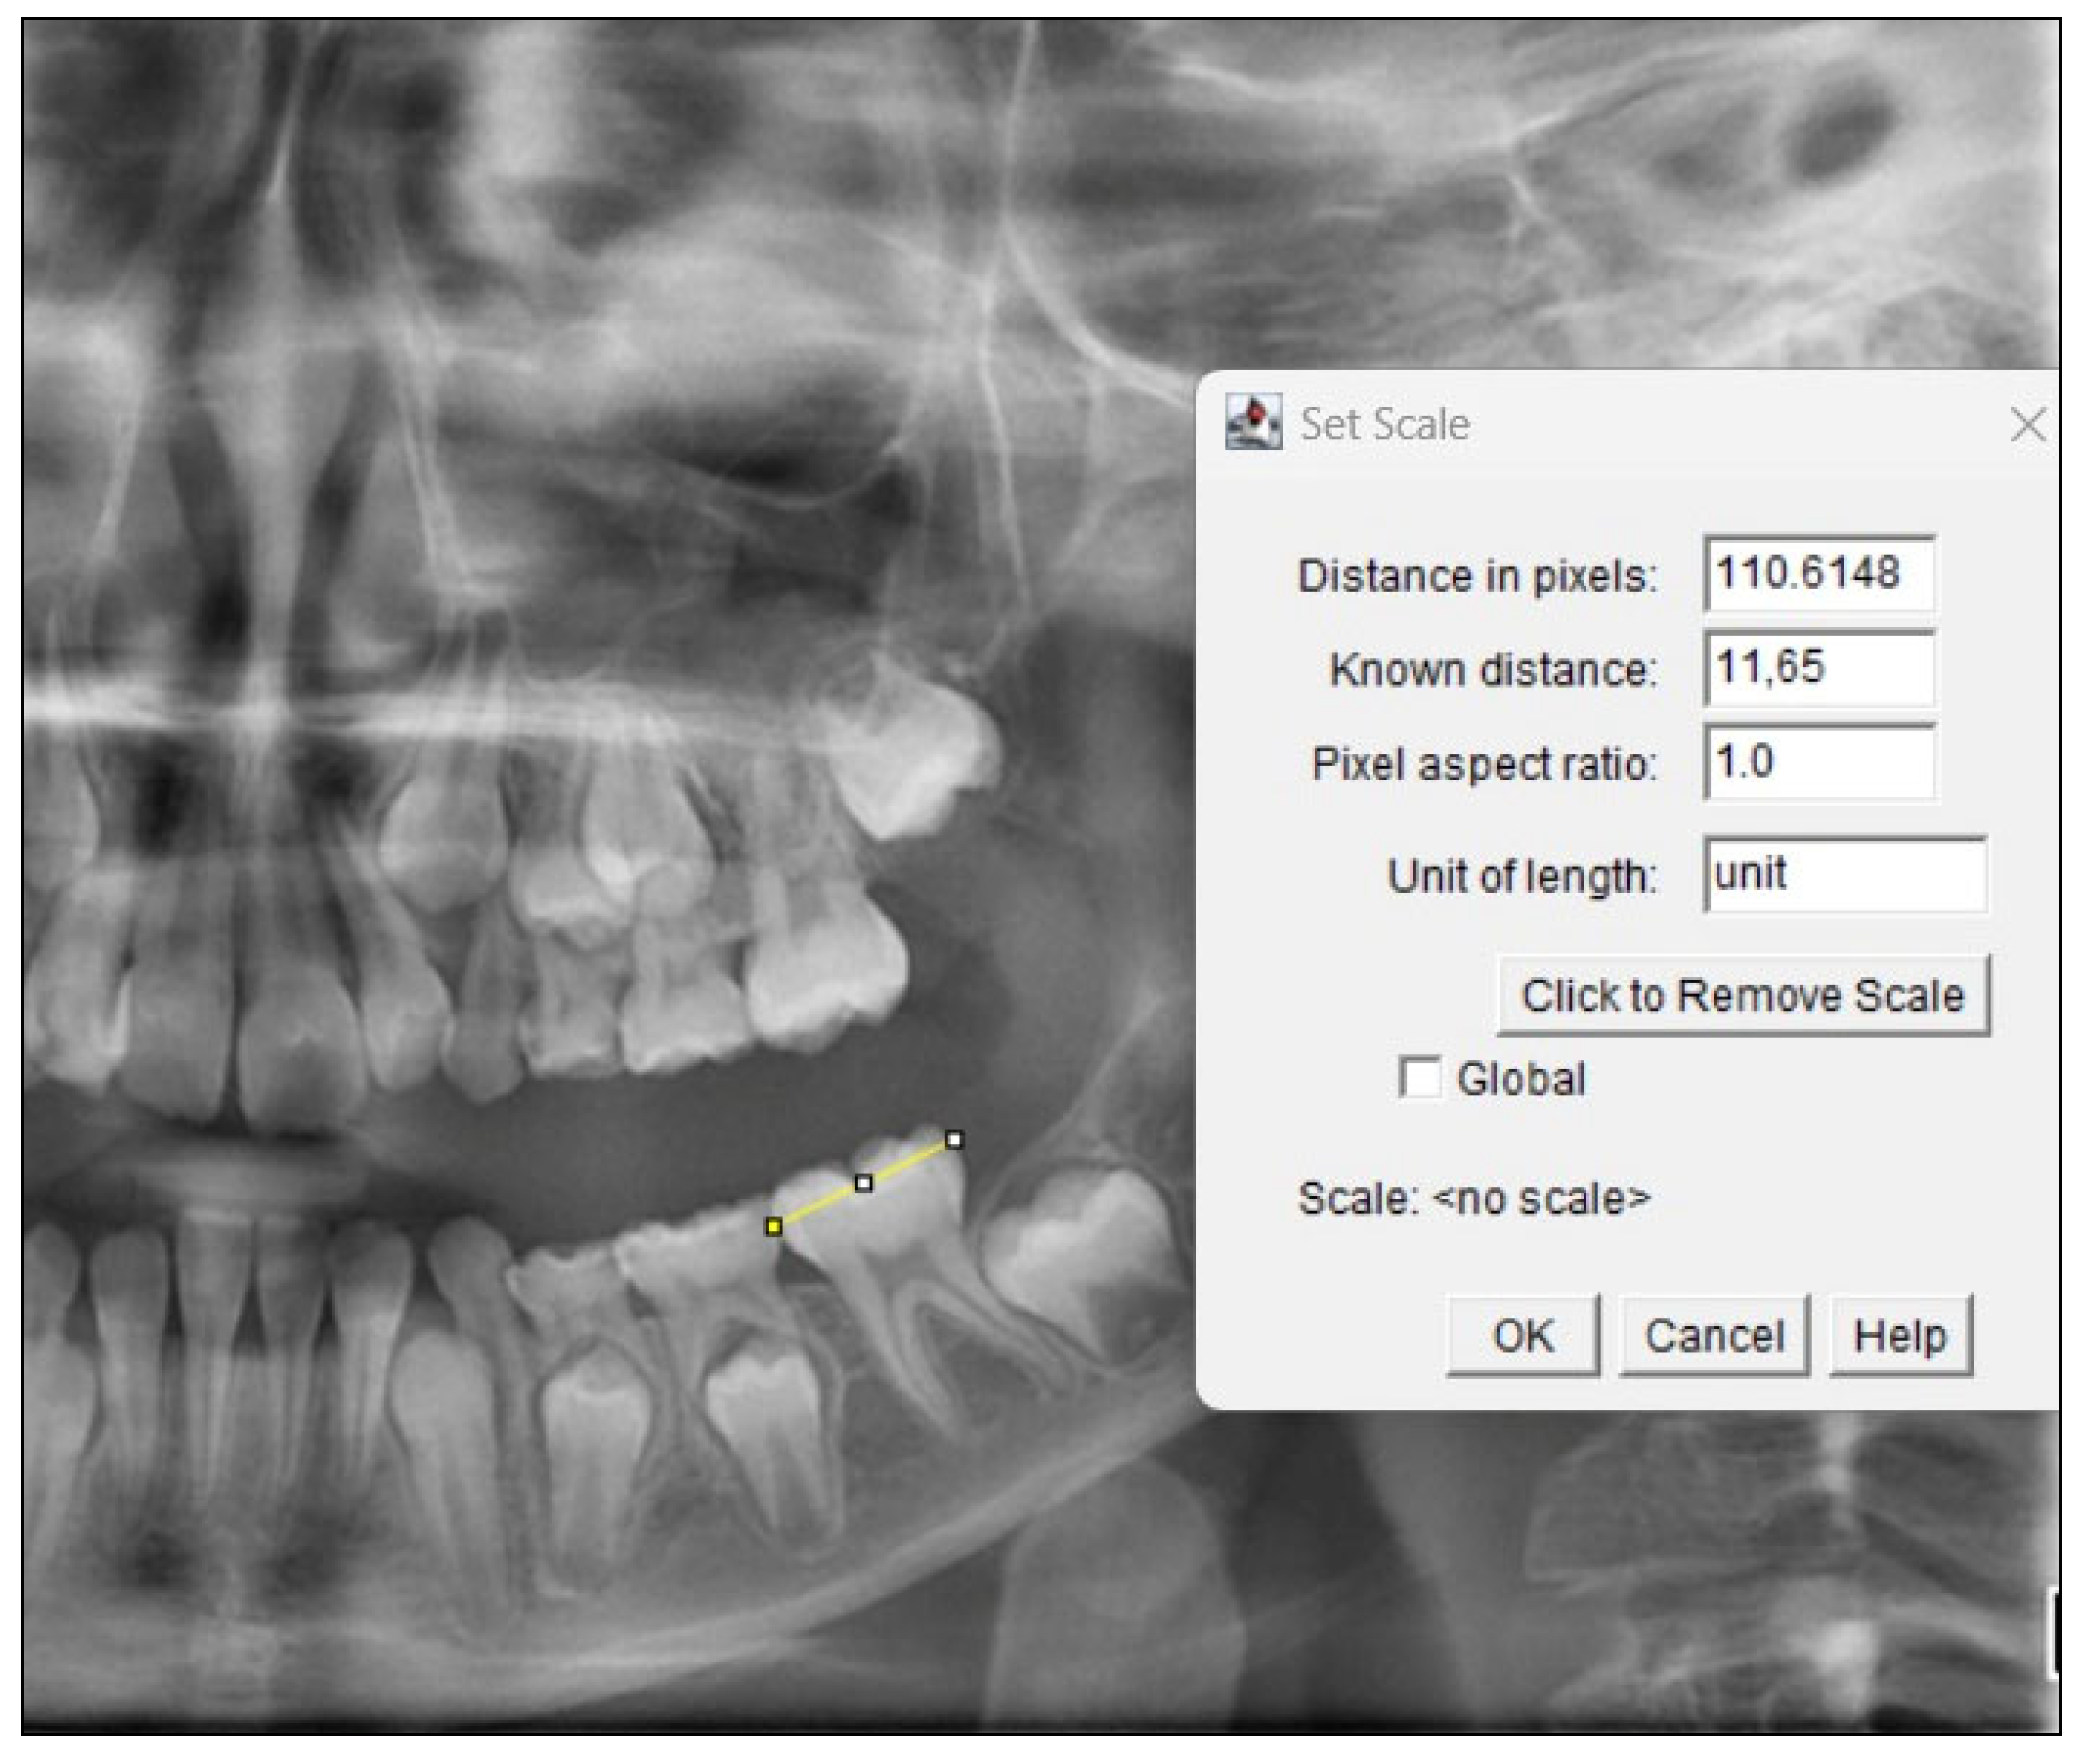

2.4. Fractal Analysis